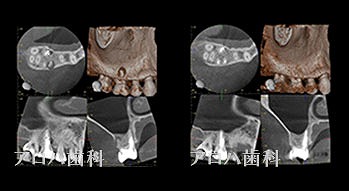

マイクロスコープ(顕微鏡)、レントゲン、CTなどで根の形と問題点を見つけます。診断無くして治療無し。診断結果にて患者さまそれぞれに合わせた治療方法や治療計画を立てていきます。

- 根の形態を把握するためのCT撮影

透過像が消失したケース

case1

初回根管治療

1年予後

治療回数1回